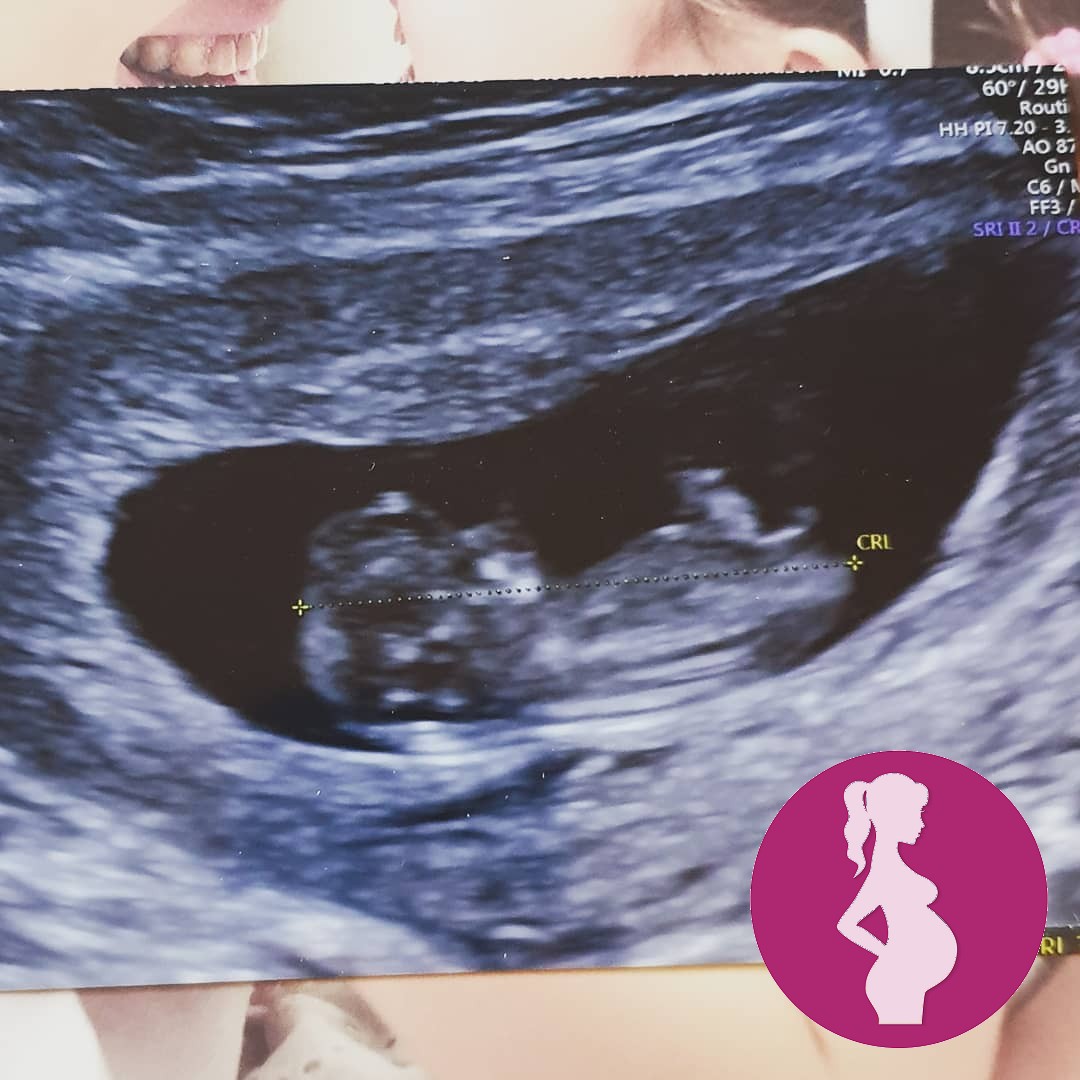

Tuesdays private 10 week scan ❤

There was an awful 30 second pause before the ultrasound technician found the heartbeat and we really feared the worst for a moment 🙈

But thankfully heartbeat was nice and strong and growth is on track (a couple of days ahead) we even saw him/her wiggling about ❤

We are now on yet another fortnight countdown to the next scan which is an NHS one at 12w2d

Still keeping everything crossed that he/she continues to stick around 🤞🤞